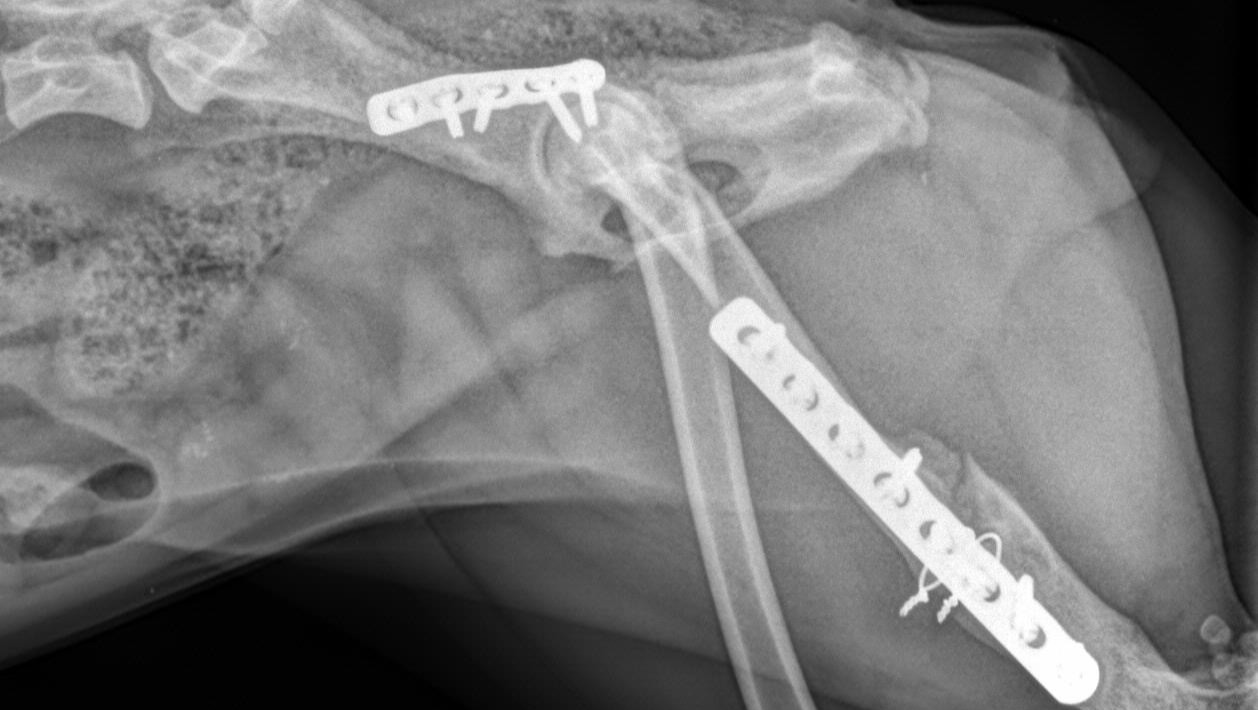

One year ago, we shared the story of a little dog in Puerto Rico who had nearly given up hope. Juanita was found lying on the side of the road in the blistering heat, unable to move after being hit by a car. She had multiple fractures in her pelvis and femur, and her tail was so badly damaged it required amputation. Someone had left a solo cup with water nearby, but she was too broken and weak to reach it. Cars drove past her for days, and when Ruby finally arrived to rescue her, she could barely lift her head. The look in her eyes said it all—she had been waiting for someone to finally care.

Thanks to the generosity of so many kind people, we were able to get Juanita into emergency surgery and start her on the long path toward recovery. Against all odds, she survived. Our on the ground director in Puerto Rico, Ruby, spent many long days and nights caring for Juanita through those first few scary months. Once she was stable enough, she made the journey from Puerto Rico to Colorado, where our rescue founder, Ela, welcomed her into her home.

But Juanita’s story isn’t over yet. Earlier this year, Juanita needed another surgery on her leg to support her recovery and give her the best chance at a healthy future. She has been incredibly brave through every procedure, every setback, and every step forward. While she continues to improve, her medical costs have added up significantly once again. Between her additional surgery, ongoing care, training, and recovery, the expenses have exceeded what our small rescue can cover on our own.